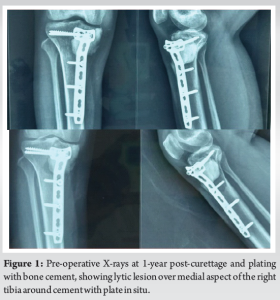

A 28-year-old female, previously treated for GCTB of the right proximal tibia with curettage, cementing, and plate stabilization in 2020, presented to our outpatient department with complaints of pain in right leg while walking since October 2021. There was no history of trauma and no associated fever, weight loss, or other constitutional symptoms. Local examination revealed tenderness over the anteromedial aspect of the proximal tibia with a local rise in temperature and a single healed previous surgical scar with no discharge, accompanied by painful terminal restriction of knee range of motion. Plain radiography of right knee was suggestive of lytic lesion over medial aspect of the right tibia around cement with plate in situ and magnetic resonance imaging (MRI) right knee was suggestive of recurrence of the tumor with no breach in joint line and no involvement of neurovascular structures (Fig. 1).